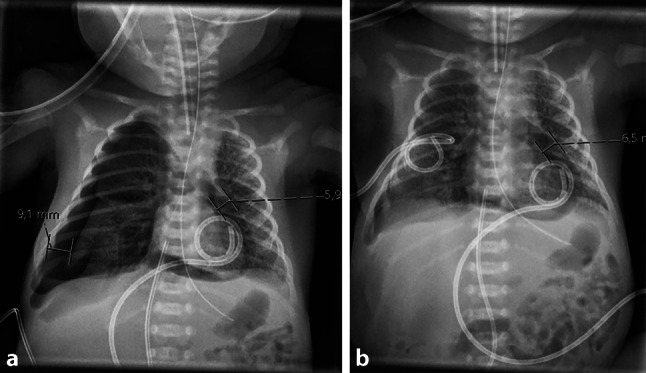

本报告强调了在潜在的心循环损害发生之前,超声心动图对心包积气的早期和异常检测。当常规超声心动图显示心脏出现困难时,在鉴别诊断中考虑心包积气是很重要的。心包积液死亡率高,可通过立即插入心包导管进行有效治疗。

This report highlights the early and unusual detection of a pneumopericardium by echocardiography prior to potential development of cardiocirculatory compromise. It is important to consider pneumopericardium into the differential diagnosis when difficulties arise in the visualization of the heart by conventional echocardiography. Pneumopericardium is associated with a high mortality rate and may be effectively treated by immediate insertion of a pericardial catheter.